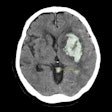

37-year-old man with history of broken needle proximal to the right elbow while injecting heroin. Anterior-posterior x-ray view of right humerus shows three linear hyperdensities in the soft tissues of the arm (arrows). Image courtesy of RSNA."In some cases, we found septic emboli in the lung or brain," Flores said in a statement released by the RSNA. "As these patients start having to access larger veins, they become more prone to these types of infections."